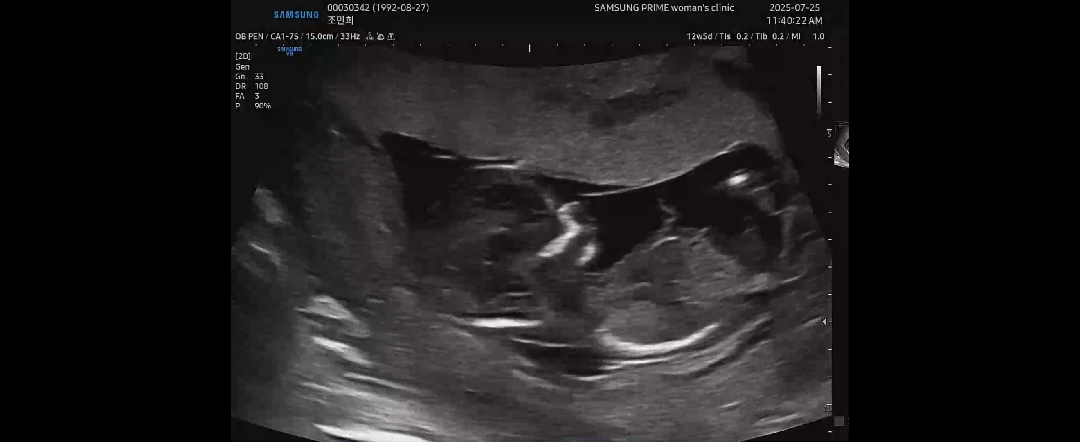

12주5일차인데요 다리는 양반다리하고잇대요 각도법좀봐주세용